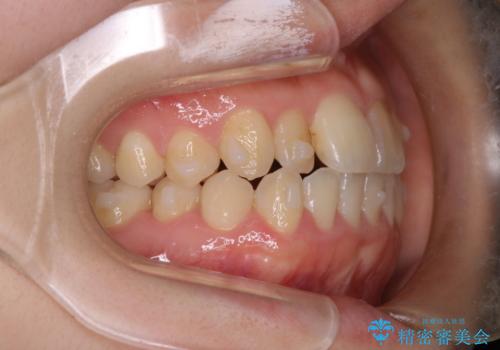

【インビザライン】前歯のがたつきを目立たない装置で治療

- 前歯の叢生を主訴に来院されました。目立たない装置を希望されたためインビザラインで治療を行いました。

IPRと拡大をし、叢生を治しました。右上2番は反対咬合でしたが短期間できれいに治りました。